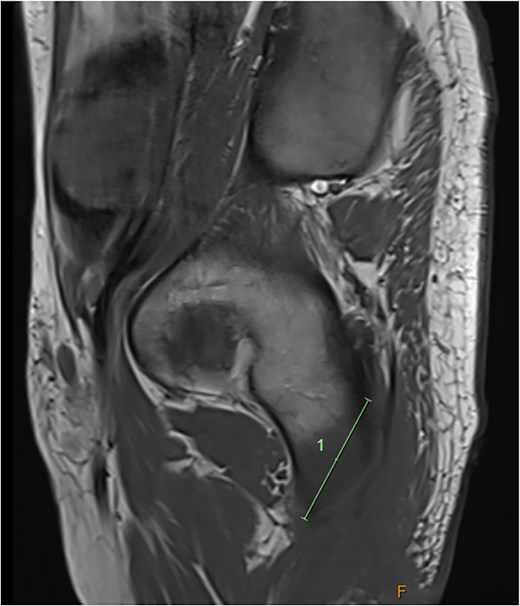

He was admitted to the Plastic and Reconstructive Surgery service for investigation and multidisciplinary management. Initial blood tests demonstrated mild anaemia, mildly elevated white cell count. His C reactive protein was 39. Liver and renal function tests were normal. Magnetic resonance imaging (MRI) demonstrated features of osteomyelitis within the left ischial tuberosity (Fig. 1) and bony involvement extending to the inferior pubic ramus (Fig. 2). Surgical biopsy was performed, with confirmation of osteomyelitis and deep tissue infection. Growth of staphylococcus epidermis and streptococcus anginous was demonstrated in pressure wound and bone chip samples.

Axial MRI image demonstrating loss of normal T1 bone marrow signal is demonstrated involving the left ischial tuberosity. Findings in keeping with osteomyelitis.